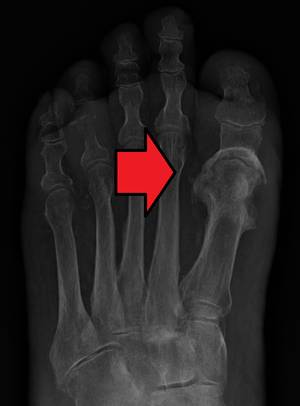

第一趾的骨髓炎